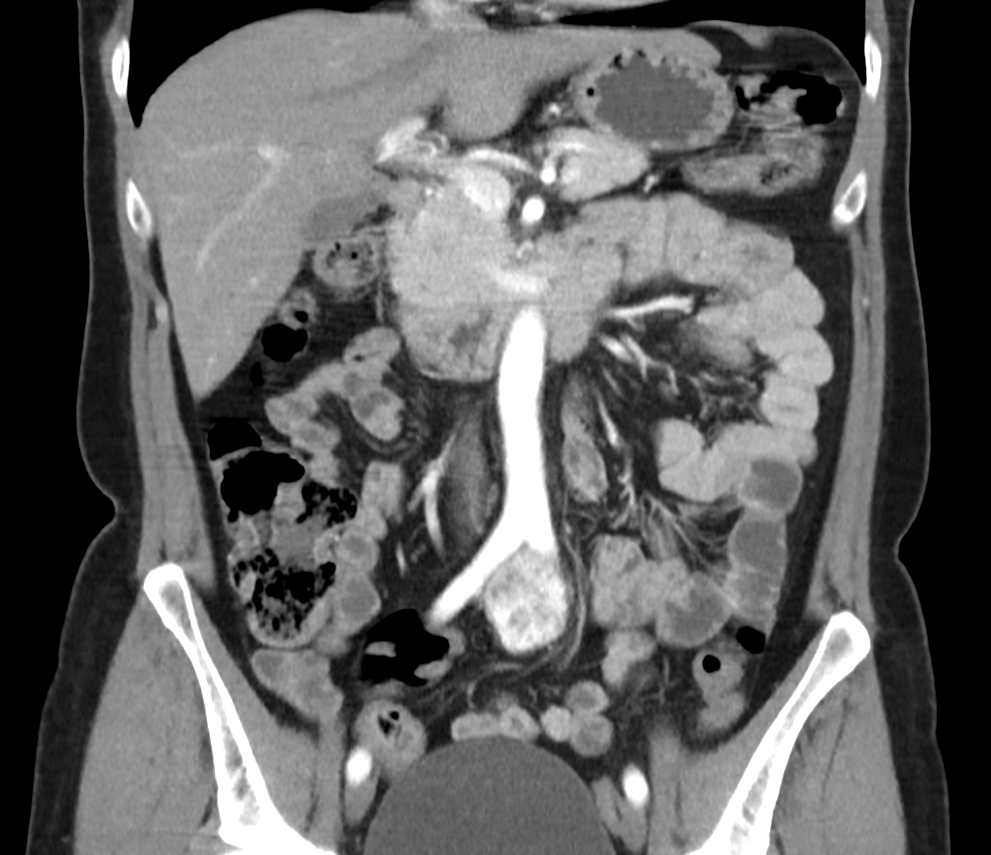

Материал и методы. В исследование включены 63 пациента с РППОК, которым в 2023–24 гг выполнена лапароскопическая правосторонняя гемиколэктомия (ЛПГКЭ) с ТМКЭ и D3-лимфодиссекцией. Всем проводили колоноскопию с подслизистым введением ICG проксимальнее и дистальнее опухоли. Доза ICG определялась эмпирически (группа 1, n=27) или индивидуально на основе площади висцерального жира (ПВЖ) по данным КТ (группа 2, n=36) – 1 мг/100 см2 ПВЖ. Успешность картирования оценивали по пятиуровневой шкале.

Описание клинического случая. Представлен случай хирургического лечения параганглиомы органа Цукеркандля у пациентки 52 лет. Установлено тесное прилежание опухоли к бифуркации аорты, что потребовало расширенно-комбинированного удаления опухоли с резекцией бифуркации аорты и восстановления магистрального кровотока бифуркационным аорто-общеподвздошным аллопротезированием (PtFe-кондуит). Послеоперационный период протекал гладко. После выписки из стационара пациентка в удовлетворительном состоянии находится под динамическим наблюдением.